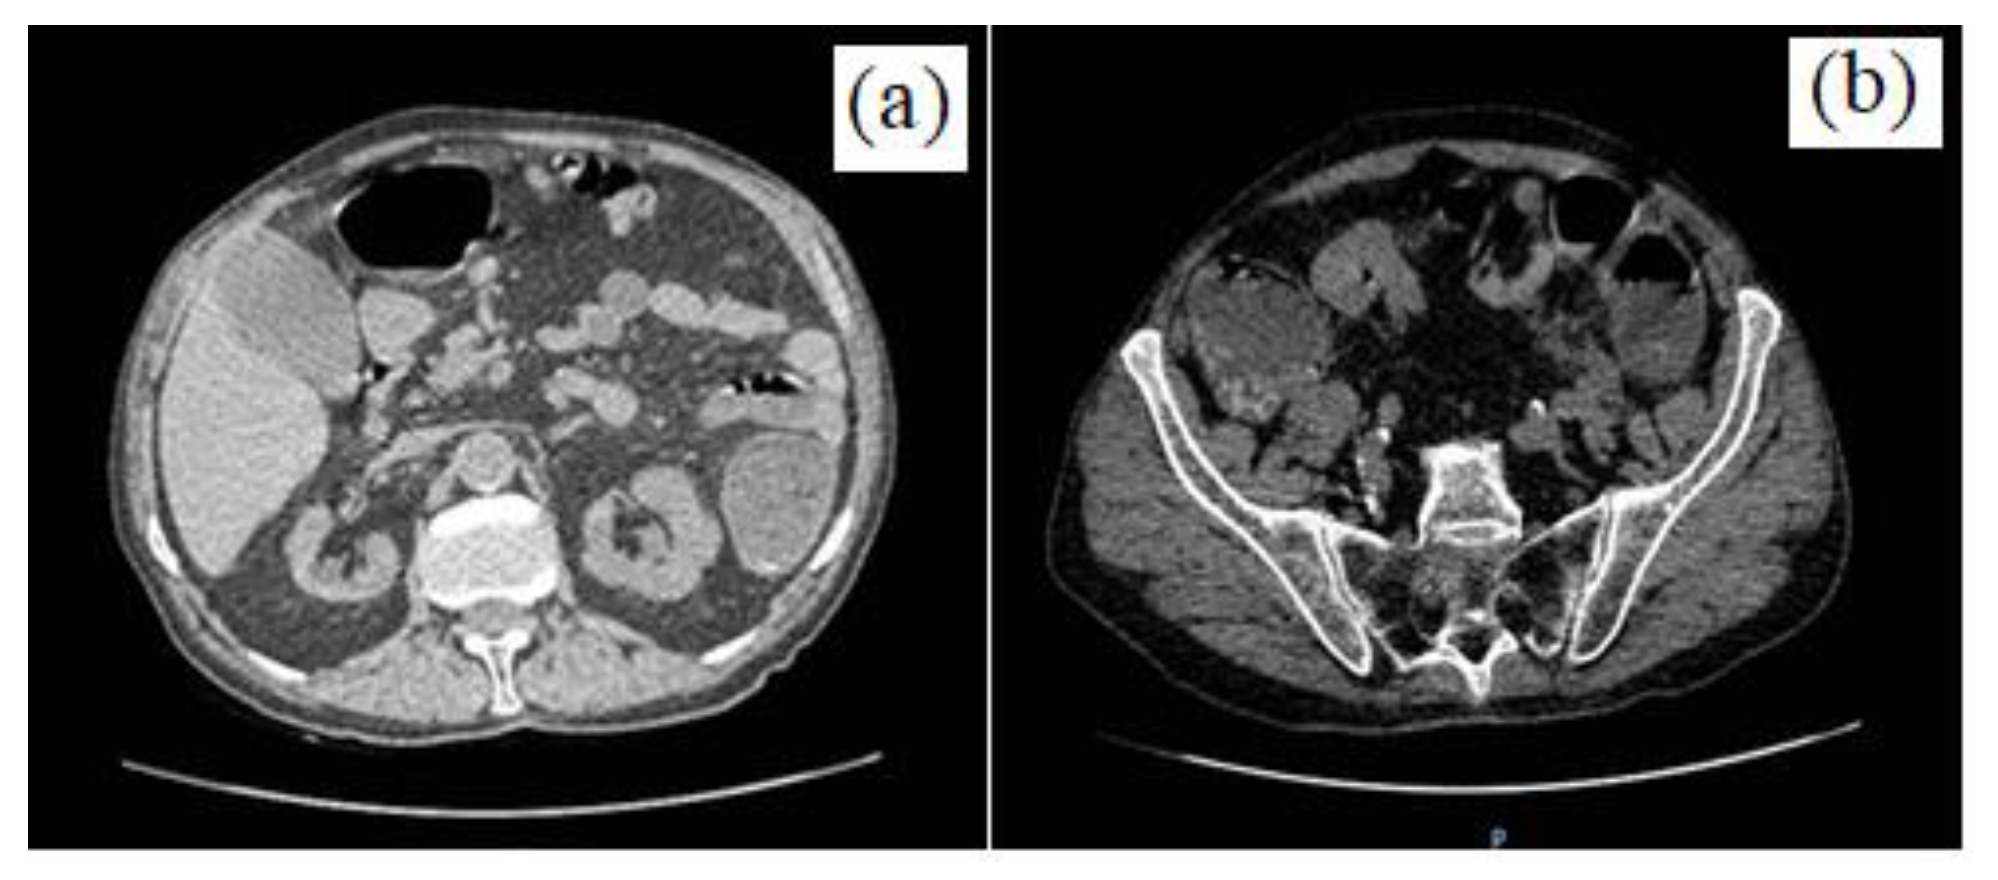

A Rare Complication in a COVID-19 Positive Patient with Sigmoid Colon Cancer-Hemoperitoneum Due to Gallbladder Necrosis Following Micro-Thrombosis

- The confirmation by histopathological examination of the existence of micro-thrombi in the gallbladder vasculature, with necrosis and its perforation, supports the recent studies that mention the occurrence of coagulation disorders in Covid-19-positive patients.